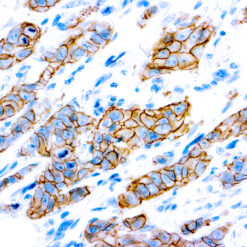

Solitary fibrous tumor (SFT) is a fibroblastic neoplasm of variable biologic potential that can arise at a wide range of anatomic sites. Almost all cases of (98%) including conventional, cellular, atypical, and malignant variants showed nuclear expression of STAT6. Staining for STAT6 was usually diffuse: 68% of cases showed reactivity for STAT6 in 75% of tumor cells. Further, the intensity of staining was strong in 67% of cases, moderate in 25%, and weak in only 7%. The heterogeneity of staining, both in terms of extent and intensity, which may be because of uneven tissue fixation or loss of antigenicity in older cases for which the unstained slides were stored for extended periods of time. All other tumor types examined were negative for STAT6, except for three dedifferentiated liposarcomas and one deep fibrous histiocytoma, which showed weak staining. STAT6 is therefore a highly sensitive and almost perfectly specific immunohistochemical marker for SFT, and can be helpful to distinguish this tumor type from histologic mimics.